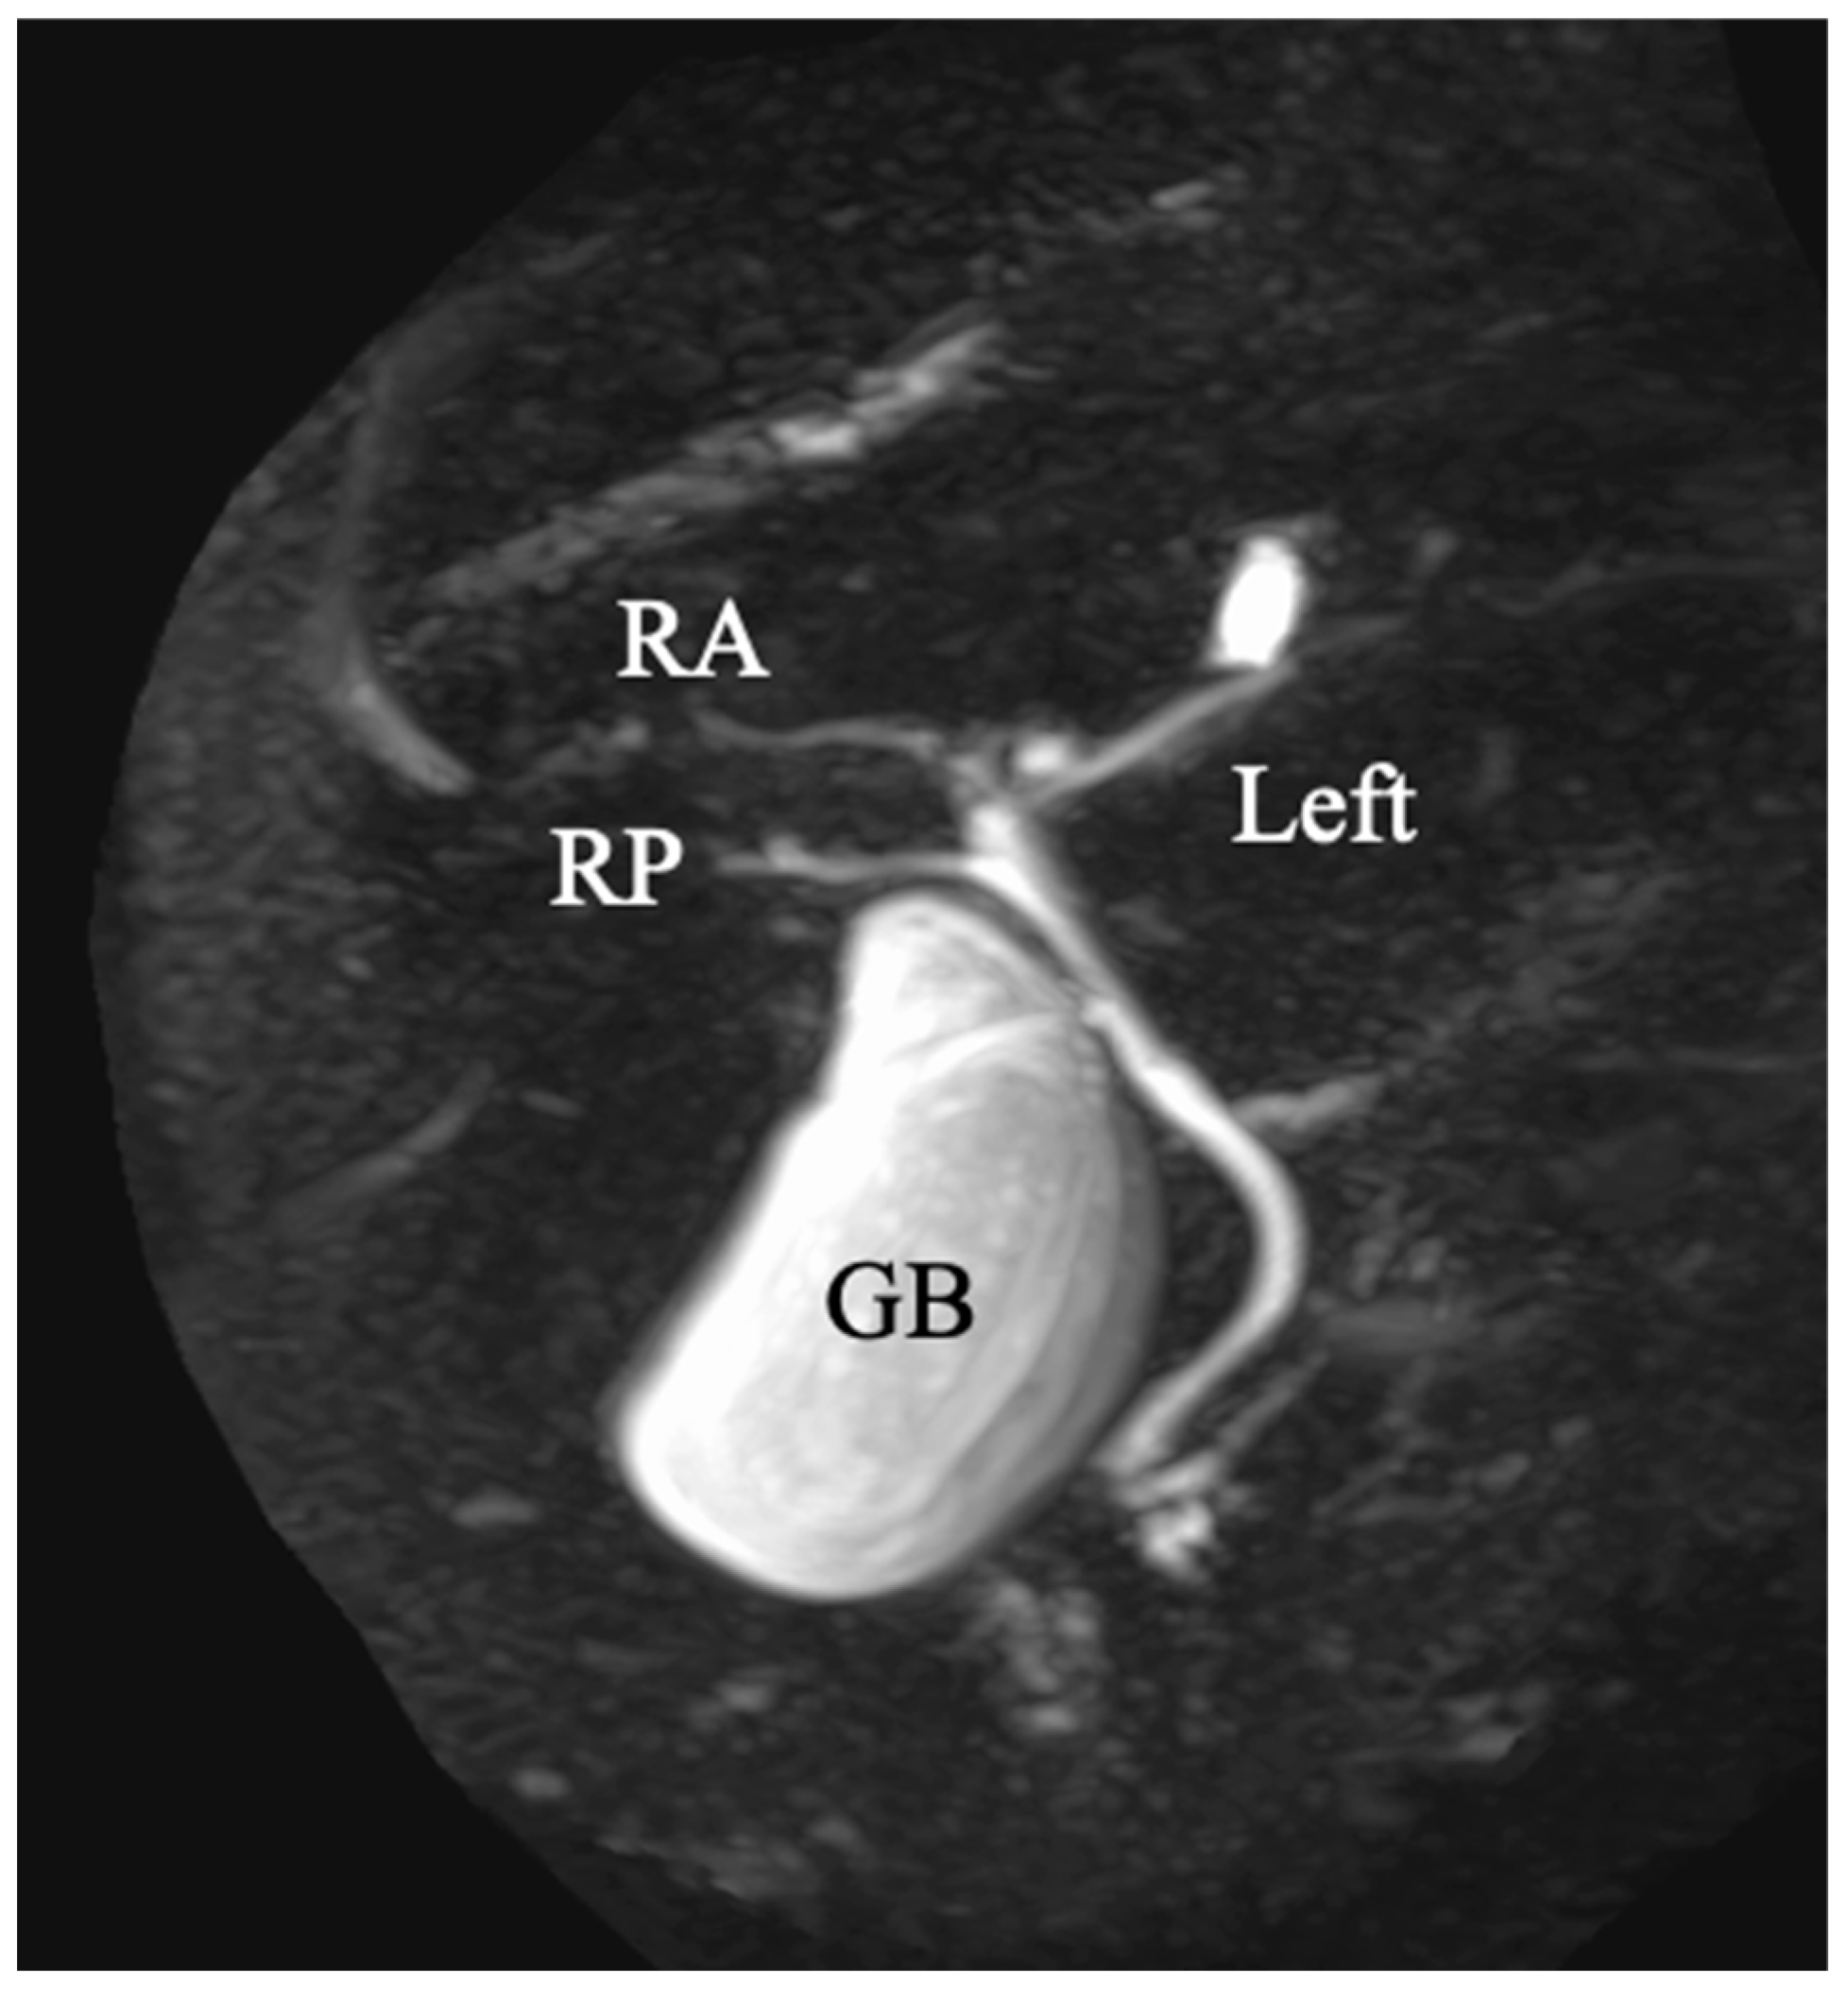

2. Case Report